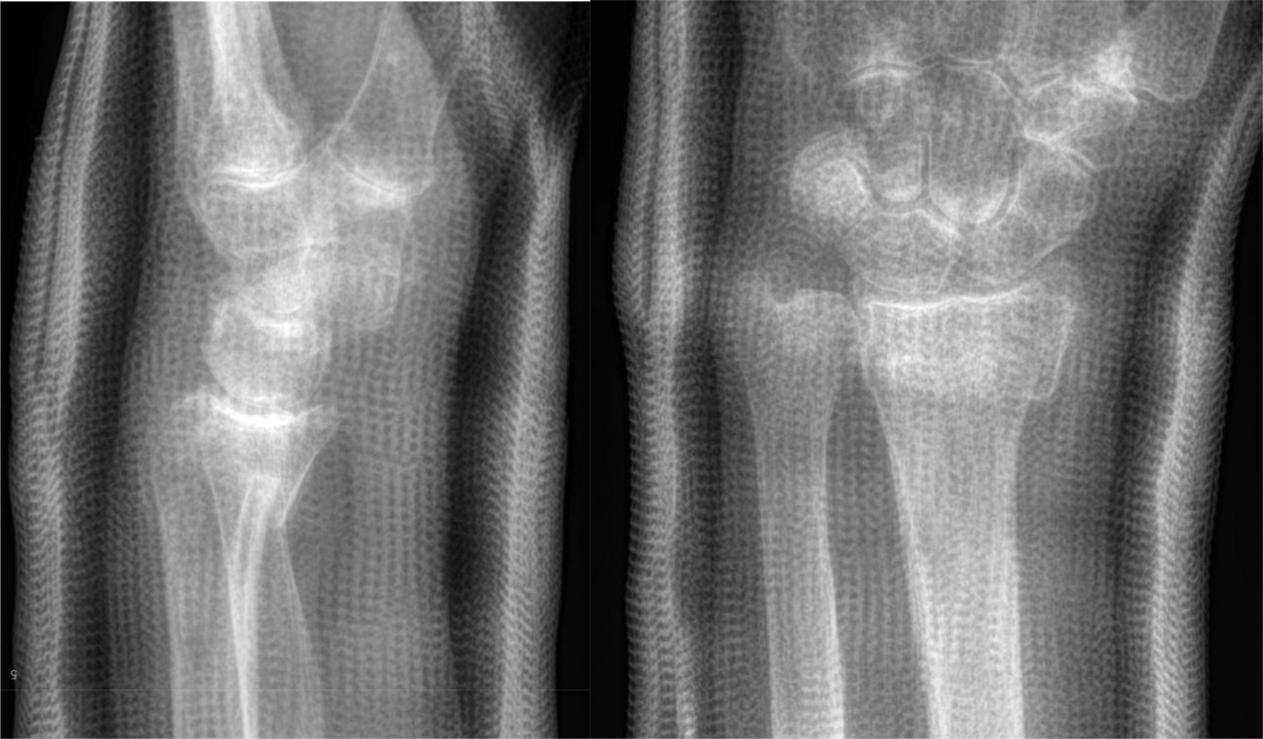

A 63-year-old active female physiotherapist falls from standing and presents to the emergency department with a moderately displaced extra-articular distal radius fracture. On postreduction radiographs, the dorsal tilt is neutral, radial inclination is 15 degrees and the distal radius is 5 mmshortened ( Fig. 1 ). She strongly requests “anatomic reduction” and fixation as she fears the slightest malunion may jeopardize her function. Opting for shared decision-making, the main question arises: What radiographic parameters are most predictive of patient-reported outcomes?

Fig. 1, Postreduction radiographs.